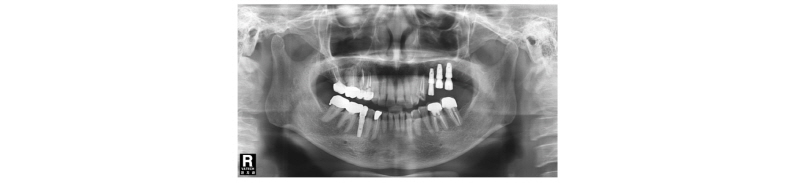

Fig. 1. First visit. Panoramic x-ray view. |

Fig. 2. Pre-Op. Panoramic x-ray view. |